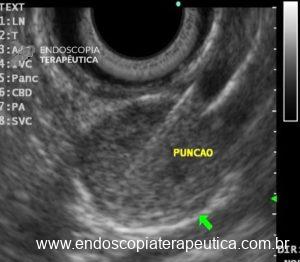

Assim sendo, obter um diagnóstico etiológico apropriado da SEL passa a ser fundamental para estabelecer a melhor conduta. Diante das ferramentas disponíveis para este fim, a aquisição de tecido através da ultrassonografia endoscópica (EUS-TA) é a mais comumente utilizada, seja pela aspiração por agulha fina (FNA) ou pela biópsia por agulha fina (FNB).